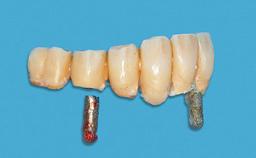

Surgical treatment of a 32-year old, healthy and non-smoking female who required removal and replacement of a lateral maxillary incisor due to internal root resorption. The inflammatory process caused a reduction of the crestal bone level on the distal side of the tooth necessitating an augmentation procedure to meet the patient's high esthetic demands. Due to the high smile line, the thin soft-tissue biotype and triangular-shaped teeth several esthetic risk factors are present.

After flapless tooth removal and a healing period of 6 weeks a diameter-reduced two-piece implant is placed. The bone defect on the facial aspect is corrected with a contour augmentation using autologous bone chips covered with DBBM particles and a collagen membrane according to the Guided Bone Regeneration (GBR) approach.